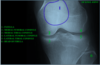

1

patella

2

medial femoral condyle

3

medial tibial condyle

4

lateral femoral condyle

5

lateral tibial condyle

6

head of fibula

Yellow

medial femoral condyle

orange

lateral femoral condyle